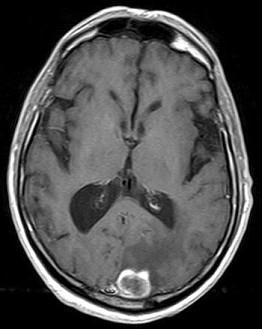

问题 男,77岁,胃癌术后2年,头痛1月,请结合影像图像选择最可能的诊断()

选项 A.脑脓肿 B.松果体瘤 C.神经胶质瘤 D.胃癌脑转移 E.脑膜炎

答案 D